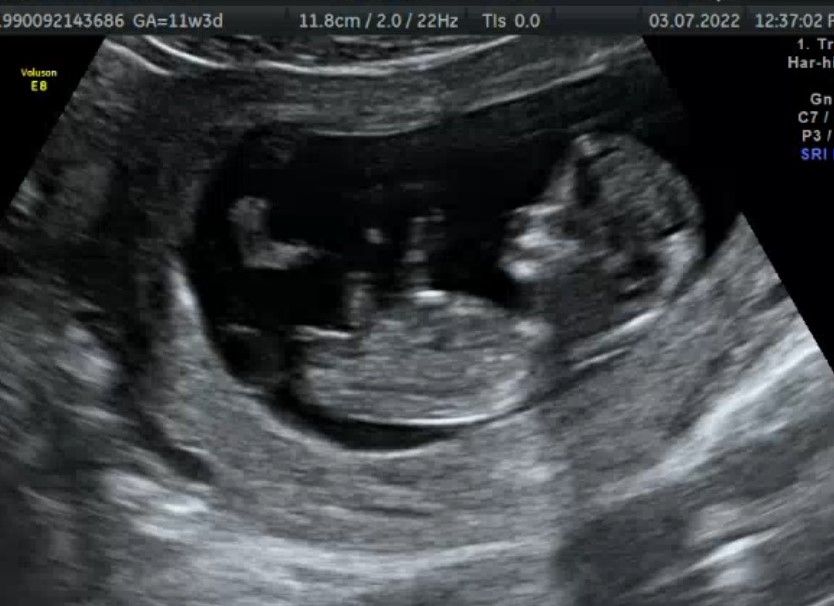

Девчушка 🎀

Если не секрет узнали кто у Вас? У меня узи очень похоже с Вашим.думаю девочка